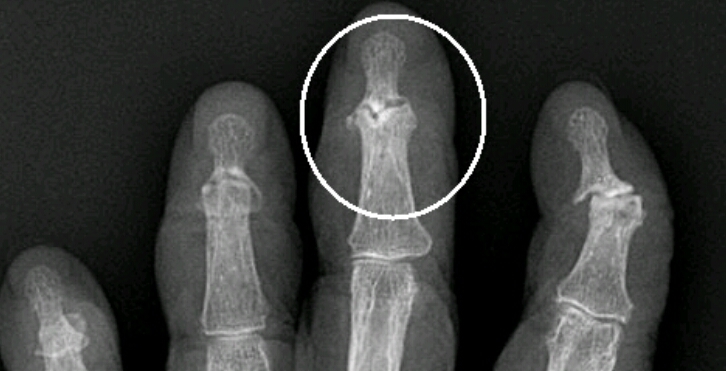

Name the feature and name the disease (be specific).

gull wing sign

erosive arthritis